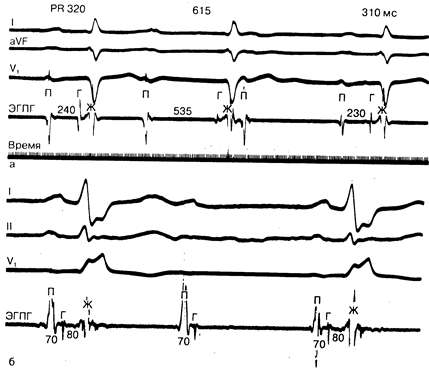

Блокада сердца II степени (промежуточная атриовентрикулярная блокада) возникает в том случае, когда часть испускаемых импульсов не достигает желудочков. Атриовентрикулярная блокада типа Мобитца I, один из вариантов атриовентрикулярной блокады II степени (атриовентрикулярная блокада Венкебаха), характеризуется прогрессивным увеличением интервала Р—R прежде, чем проведение предсердного импульса станет невозможным (рис. 183-7, а). Продолжительность следующей затем паузы меньше, чем полной компенсаторной паузы, т. е. менее двух обычных синусовых интервалов. При этом величина интервала Р—R первого импульса меньше величины этого интервала у последнего предсердного импульса, после которого возникновение зубца Р блокируется. Этот тип блокады практически всегда является следствием нарушения проводимости на уровне предсердно-желудочкового узла и не сопровождается изменением ширины комплекса QRS. Чаще всего он встречается в виде транзиторного расстройства ритма сердца при инфаркте нижней стенки миокарда или при передозировке таких препаратов, как сердечные гликозиды, блокаторы, а иногда и антагонисты кальциевых каналов. Данный тип блокады можно наблюдать и у здоровых людей с повышенным тонусом блуждающего нерва. В редких случаях блокада Мобитца типа I может прогрессировать вплоть до полной блокады сердца. И даже если это происходит, то нарушение проводимости хорошо переносится пациентом, поскольку благодаря механизму ускользания в проксимальной части предсердно-желудочкового пучка (Гиса) обычно формируется подчиненный водитель ритма, обеспечивающий стабильный режим сердечных сокращений. В результате этого больные с атриовентрикулярной блокадой II степени типа Мобитца I, как правило, не требует интенсивной терапии. Режим лечения больного зависит от работы желудочков и тяжести симптомов. Если желудочковый ритм адекватен и не приводит к появлению у пациента клинических симптомов, то достаточно установить за ним наблюдение.

При атриовентрикулярной блокаде типа Мобитца II нарушение проводимости развивается внезапно, без предварительного изменения интервала Р—R (см. рис. 183-7,6). Подобная ситуация возникает как следствие поражения системы Гиса—Пуркинье и часто сопровождается расширением комплекса QRS. Очень важно своевременно распознать блокаду этого типа, поскольку она имеет тенденцию к прогрессированию вплоть до полной блокады сердца. Подчиненный водитель ритма, включающийся в нижних отделах системы Гиса—Пуркинье вследствие ускользания, обладает нестабильным, медленным ритмом. Вот почему в этом случае обязательна имплантация кардиостимулятора. Блокада типа Мобитца II может осложнить течение переднеперегородочного инфаркта миокарда, а также первичных или вторичных склеродегенеративных поражений или кальцификации фиброзного скелета сердца.

Рис.183-7. Тип блокады Мобитца. а — атриовентрикулярная блокада II степени типа Мобитца I. Регистрация внутрисердечных электрограмм свидетельствует о том, что причина увеличения продолжительности интервала Р—R (320, 615 мс) находится на уровне предсердно-желудочкового узла (ПГ 240, 535 мс соответственно). (Из Josephson and Seides); б—атриовентрикулярная блокада II степени типа Мобитца II. Внутрисердечная регистрация электрограмм указывает на то, что блокада локализуется ниже предсердно-желудочкового пучка (Гиса). Обозначения: ЭГПГ — электрограмма пучка Гиса; П — предсердие; Г — пучок Гиса; Ж — желудочек.